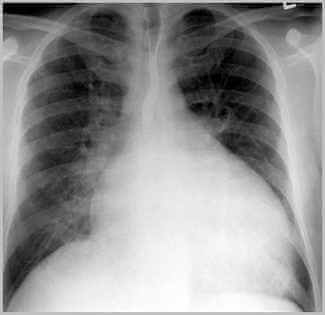

Kalp büyümesi tedavisi. Ileri derecede hasarlanmış fonksiyonlarını yerine getiremeyen kalbin göğüs boşluğundan çıkarılarak yerine başka birinden alınan ve işlevleri normal olan kabin takılması işlemidir. Kalpteki kapaklarda oluşan bazı problemlerde kalbin büyümesinde etken. Kalp büyümesinin tedavisi hastalığın altında yatan ana sebebe bağlı olarak değişir. 1 kalp büyümesinin tıbbi tedavi yöntemleri.

Kalp büyümesi tedavisinde kalp nakli tedavisi. Bunun sonucu olarak kalp büyüme yapabilir. Kalp büyümesinin tedavisi var. Yapılan test ve tetkikler sonucunda hastalığın nedeni belirlenmeli ve kalp büyümesine neden olan faktörler ortadan kaldırılmalıdır.

Bunun için öncelikle altta yatan hastalıklar tedavi edilmelidir. Iki yönlü yaklaşım tıbbi tedavi ve evde destek uygulamaları kalp büyümesi tedavisinde tercih edilen en etkin çözüm yöntemlerindendir. Kalp büyümesi tanı ve tedavisi. Kalp büyümesinin tedavisi hastanın ve hastalığın altında yatan ana veya diğer sebeplere bağlı olarak değişiklik gösterebilir.

Iki yönlü yaklaşım tıbbi tedavi ve evde destek uygulamaları kalp büyümesi tedavisinin en etkin çözüm yoludur. Her yerde olduğu gibi kalp büyümesinde de risklerin başını çekiyor. Ilaç kullanımı ile hastanın şikayetleri geçmiyor ise kalp nakli tedavisi gerekebilir. Ne kadar erken o kadar iyi kuralı kalp büyümesi sorununda da geçerli tedavisinden önce kalp büyümesine ortam hazırlayabilecek sağlık sorunlarına bakalım.